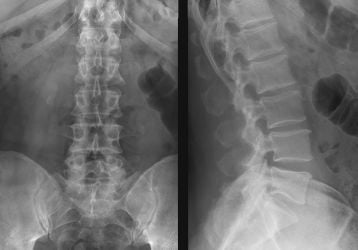

Рентген пояснично-крестцового отдела позвоночника: что показывает

Что показывает рентген пояснично-крестцового отдела. Какие проекции существуют. Примеры диагнозов видных на снимке. Как проходит процедура.